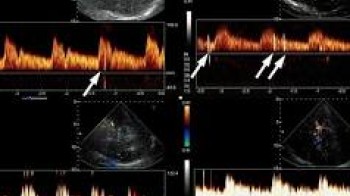

Ako je test izveden pravilno, mikromjehurići  bi trebali proći kroz pluća i biti filtrirane. Ako se pojavljuju na lijevoj strani srca ili mozga (detektovano TCD-om), potvrđuje se postojanje RLS.

Pozitivan test pokazuje da su mjehurići prešli sa desne na lijevu stranu cirkulacije, što sugeriše PFO, ASD ili drugi šant. Težina šanta se često ocjenjuje brojem viđenih mikromjehurića:

• Blagi (Grade 1-2): Pojedini mjehurići na lijevoj strani

• Umjereni (Grade 3): Umjeren broj mjehurića prelazi

• Teški (Grade 4): Velik broj mjehurića brzo prelazi, što ukazuje na veliki ili lako otvoriv šant